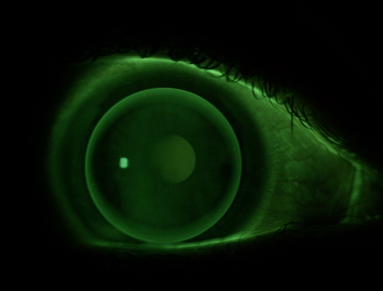

Lorsque la lentille est correctement adaptée, on observe une image fluorescente uniforme avec un bon centrage. Le mouvement de la lentille est silencieux.

goede passing flexi TC

BCR = K moyenne + 0,10 mm